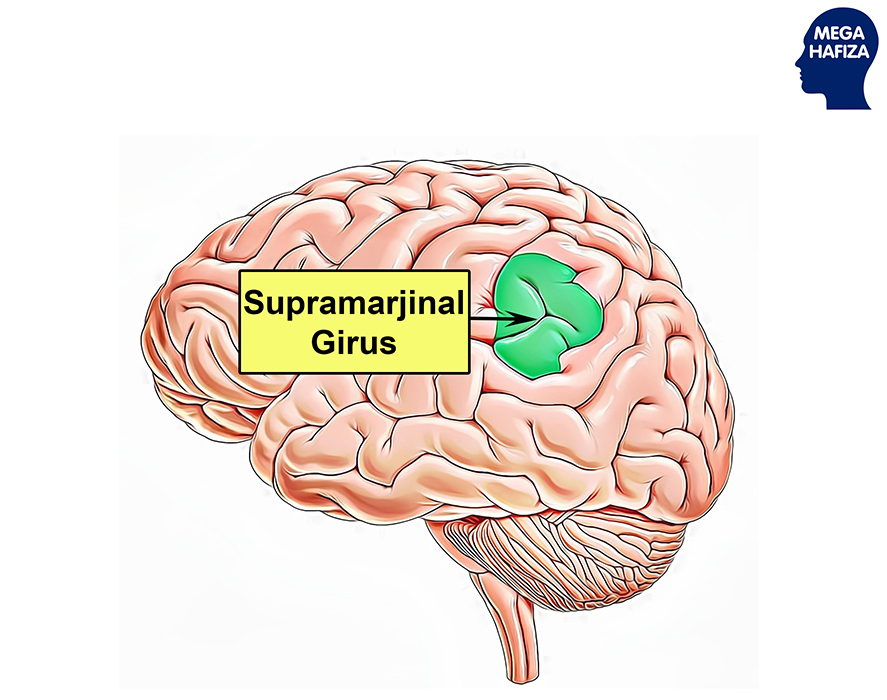

Супрамаргинальная извилина: Функции и Исследования